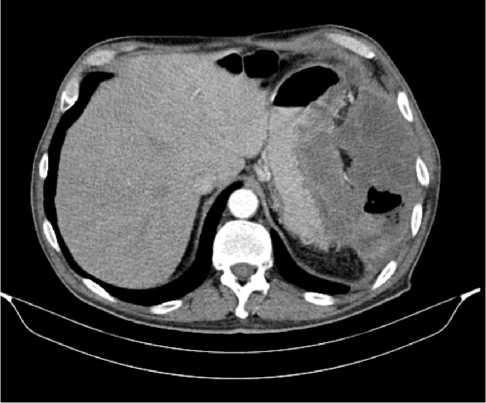

С июля 2022 г. у пациента отмечено появление эпизодов субфебрильной лихорадки. По результатам КТ органов брюшной полости от 08.2022 г. в проекции селезенки выявлена неоднородная инфильтрация с включениями, воздушной полостью в структуре, с тенденцией к отграничению и с распространением в параколическую клетчатку размерами 125 × 98 × 96 мм. Опухоль распространяется на большую кривизну желудка, вызывая утолщение стенки толщиной до 37 мм. По передней брюшной стенке справа отмечается округлое образование размерами 10 × 9 мм (рис. 5).

Рис. 5. Результаты компьютерной томографии органов брюшной полости у пациента 62 лет с диагнозом метастатический колоректальный рак с признаками микросателлитной нестабильности (август 2022 г., до лечения)

Fig. 5. Results of a CT scan of the abdomen of a 62-year-old patient with metastatic MSI-H colorectal cancer (August 2022, before treatment)

По результатам иммуногистохимического и молекулярно-генетического исследований, выявлены признаки dMMR/MSI-H (не экспрессируется MLH1) и мутация G12D в 12 кодоне гена KRAS.

По решению мультидисциплинарной комиссии, с учетом выявленного прогрессирования заболевания, его распространенности (массивный опухолевый конгломерат в левом подреберье, вовлекающий близлежащие петли кишки и дистальные отделы желудка, поджелудочную железу), ограничивающей проведение хирургического лечения, биологического статуса опухоли (dMMR/MSI-H), соматического статуса пациента ECOG-2 (обусловлен болевым синдромом), рекомендована 1 линия иммунотерапии пембролизумабом.

С 12.10.2022 пациенту выполнено 15 введений пембролизумаба с промежуточным эффектом частичный регресс.

По результатам КТ органов брюшной полости (ОБП) от 08.2023, поддиафрагмально слева сохраняется инфильтрат 79 × 46 мм, распространяется на большую кривизну желудка, брюшину, диафрагму слева и по левому фланку брюшной полости. Желудок деформирован, стенки утолщены. Парагастральная и внутрибрюшинная клетчатка слева инфильтрирована. По брюшине сохраняются образования. Эффект лечения оценен как частичный регресс (рис. 6).

Рис. 6. Частичный регресс, по данным компьютерной томографии органов брюшной полости, на фоне иммунотерапии пембролизумабом у пациента 63 лет с диагнозом метастатический колоректальный рак с признаками микросателлитной нестабильности (август 2023 г.)

Fig. 6. Partial regression according to abdominal CT scan during immunotherapy with pembrolizumab in a 63-year-old patient with metastatic MSI-H colorectal cancer (August 2023)